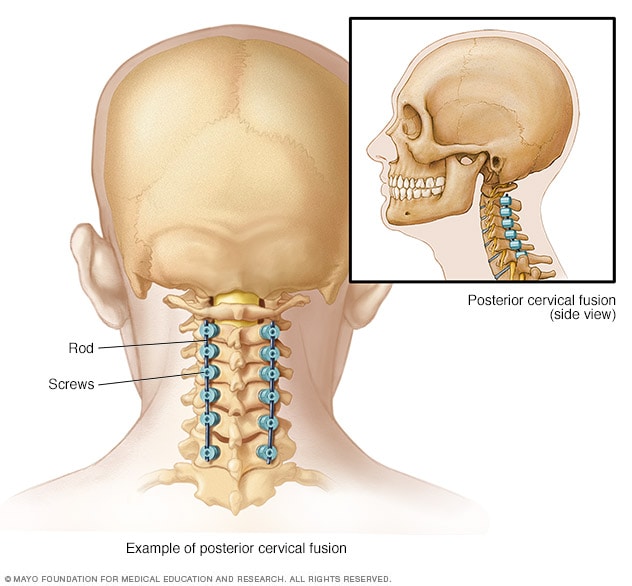

Posterior Cervical Fusion Procedure | Globus Medical

Spinal Fusion – Cedar Park, TX – Austin, TX – Spine Stabilization

Spinal fusion – Mayo Clinic